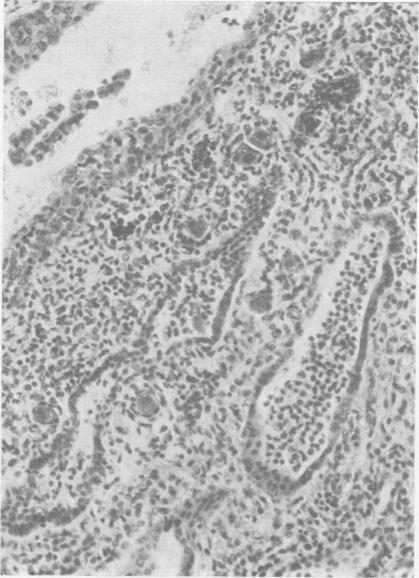

Inclusion disease in childhood.

Arch Dis Child. 1951 Dec;26(130):588-600. doi: 10.1136/adc.26.130.588.